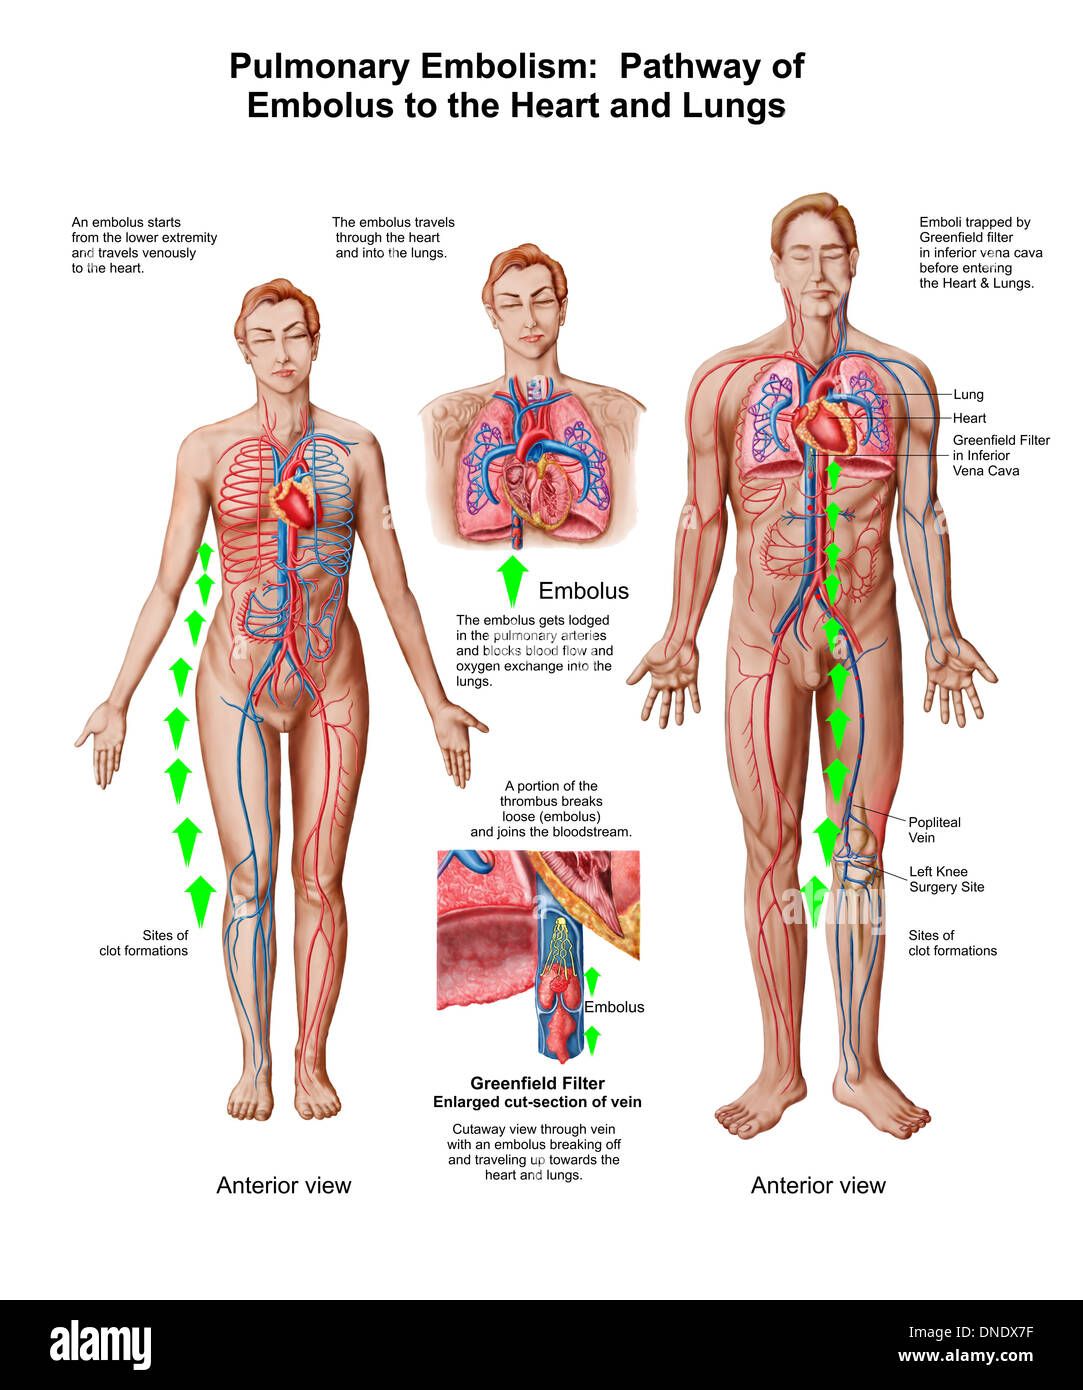

Pulmonary embolism, pathway of embolus to the heart and lungs. Stock Photohttps://www.alamy.com/image-license-details/?v=1https://www.alamy.com/pulmonary-embolism-pathway-of-embolus-to-the-heart-and-lungs-image64844851.html

Pulmonary embolism, pathway of embolus to the heart and lungs. Stock Photohttps://www.alamy.com/image-license-details/?v=1https://www.alamy.com/pulmonary-embolism-pathway-of-embolus-to-the-heart-and-lungs-image64844851.htmlRFDNDX7F–Pulmonary embolism, pathway of embolus to the heart and lungs.